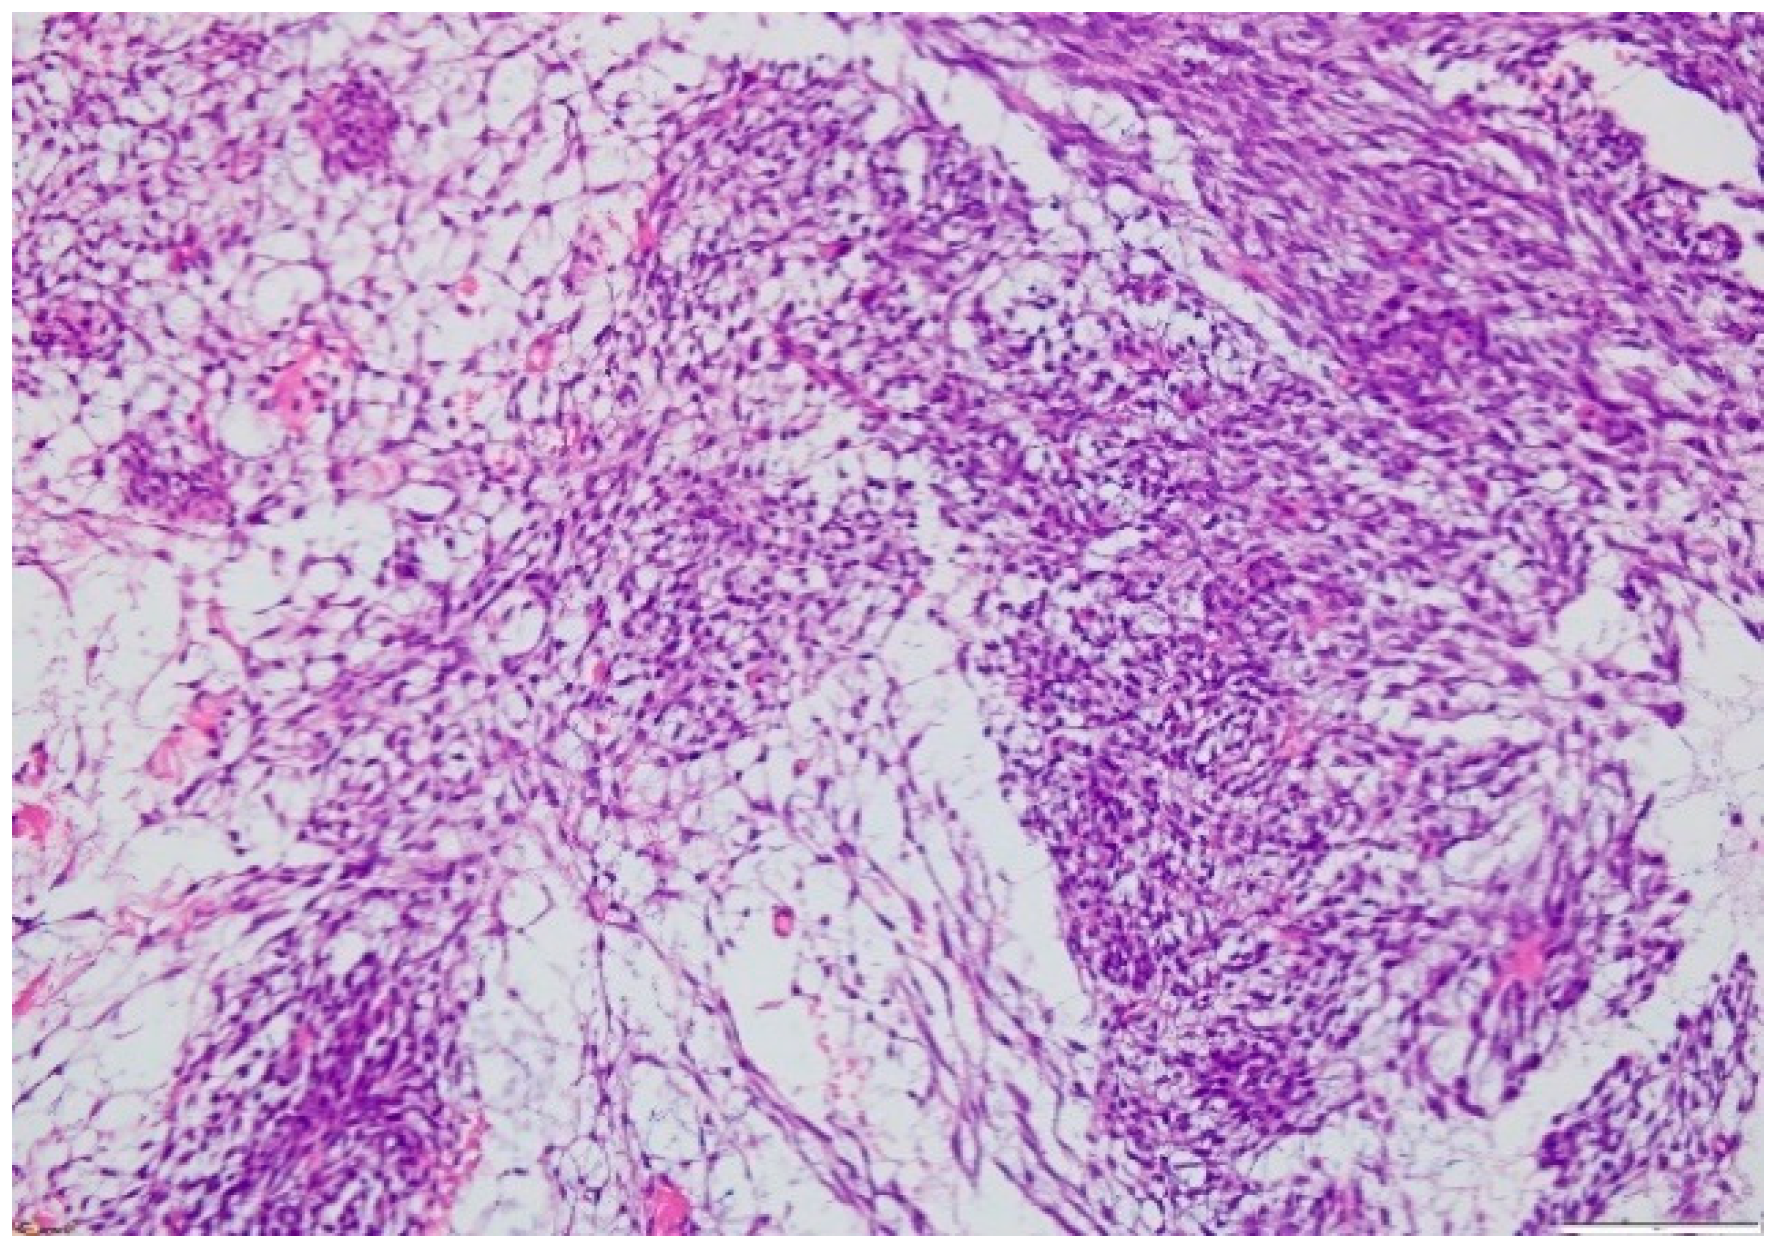

The microscopic exam of the synovial sarcoma will indicate one of the three possible variants: monophasic, biphasic or poorly differentiated. For the first variant, the cellularity is represented by spindle cells, whereas in a biphasic synovial sarcoma, there may also be epithelial cells present (Figure 8 and Figure 9). Furthermore, the microscopic exam may reveal the presence of calcifications/ossification areas in up to one-third of cases.

Figure 8.

Microscopic findings—classical synovial sarcoma with two main subtypes: biphasic and monophasic appearance, and with two typical cell types: spindle cells and epithelial cells (fusocellular proliferation with myxoid areas, detail), which is rare (HE staining, 20×).

Figure 9.

Microscopic finding—monophasic subtype of a synovial sarcoma with mesenchymal spindle cell elements and fusocellular proliferation (HE staining, 40×).